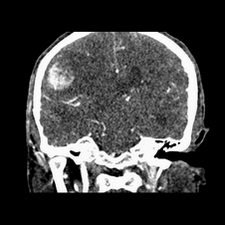

标题: CT25808:男,48岁,头痛多年,近段时间头痛加重伴步态不稳 [打印本页]

标题: CT25808:男,48岁,头痛多年,近段时间头痛加重伴步态不稳

平扫:右颞顶叶病灶呈等低密度伴大面积水肿,脑室受压变形。增强:病灶显著强化。考虑淋巴瘤或黑色素瘤。

1)不排除黑色素瘤可能;建议行mri检查。2)大脑镰下疝。3)脑积水(梗阻性)。